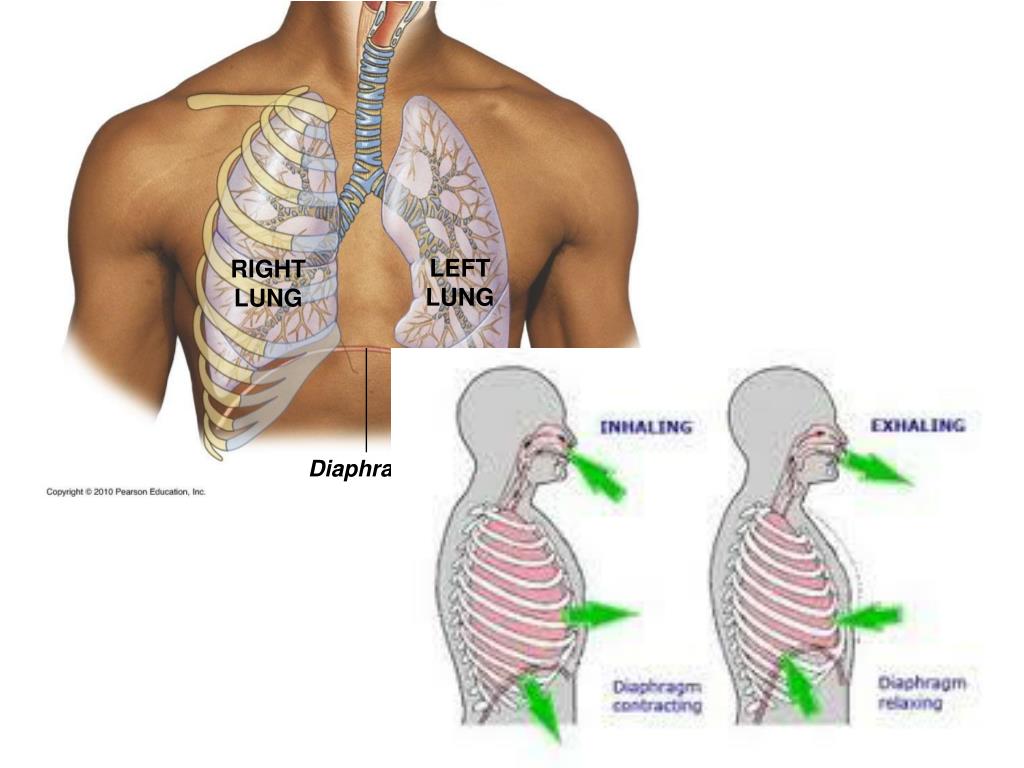

Роль легких в метаболических процессах